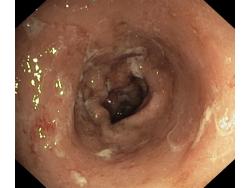

Obrazy endoskopowe

Nowotwory przewodu pokarmowego